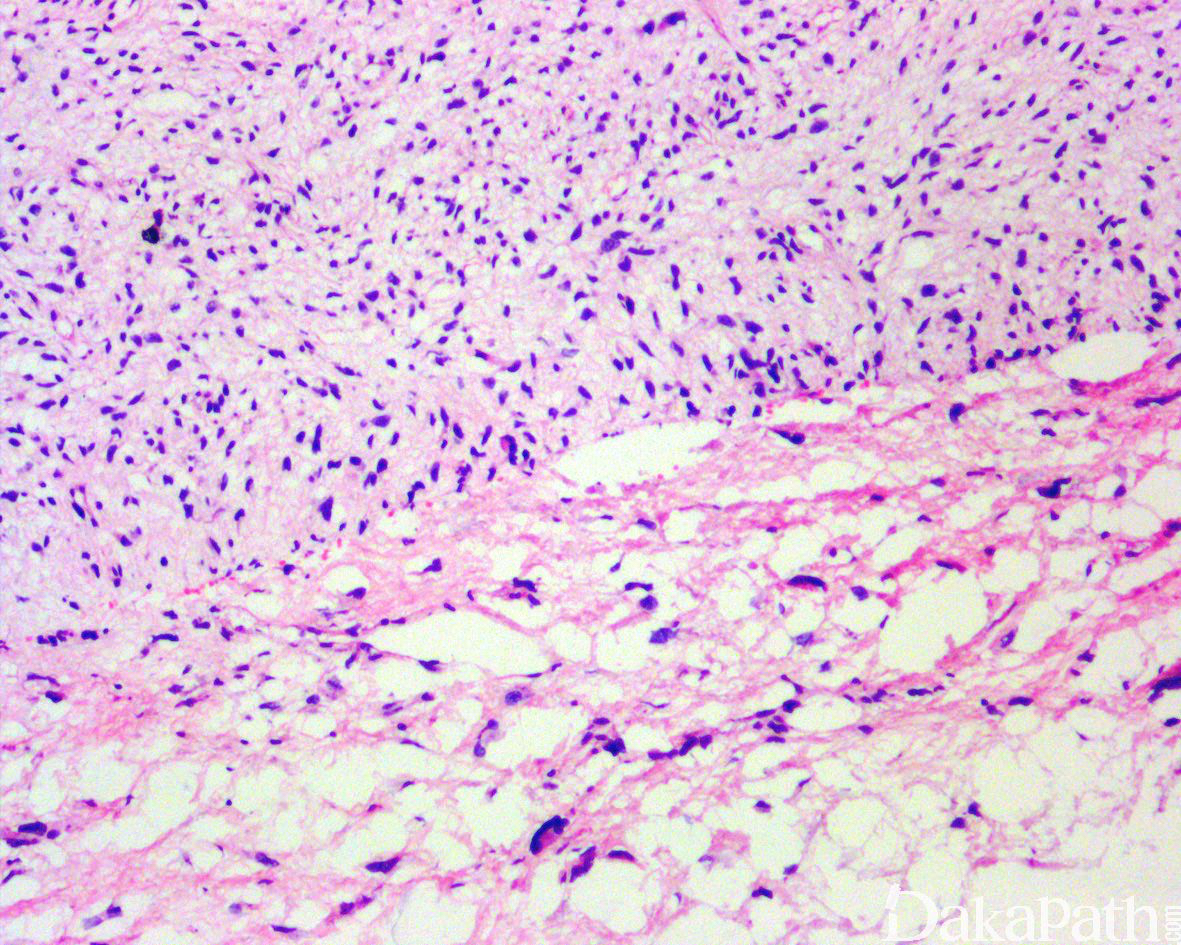

如前所述,DDLPS 组织学上通常表现为 ALT/WDLPS 成分向非脂肪源性的肿瘤成分转化,2 种成分在镜下通常分界较清楚,表现为突然的过渡;但有时可表现为逐渐的过渡或在整个肿瘤内交错的分布(马赛克样的去分化),这一情况尤其在伴有低级别去分化时常见。肿瘤可能部分带假包膜或边界清楚,但至少局部可见推挤状或浸润性边界,后腹膜的 DDLPS 常见累及周围实质器官(如肾脏等)。高分化与去分化成分的比例在不同肿瘤内多少不等,有时候即使在广泛取材的情况下高分化成分也可能完全确如,而去分化成分通常较广泛,但有时也可能仅仅不足 1 cm(又称为微小去分化)。DDLPS 中的 ALT/WDLPS 组织学类型以脂肪瘤样和硬化性为主,而去分化成分大多数表现为高级别去分化特征包括高级别多形性肉瘤样(多形性瘤细胞伴有席纹状排列类似于多形性未分化肉瘤/恶性纤维组织细胞瘤)、高级别梭形细胞肉瘤样(细胞密度较高的梭形瘤细胞伴有交错束状或鱼骨样排列类似于纤维肉瘤)以及少见的高级别圆细胞肉瘤样(弥漫的小蓝圆细胞类似于骨外尤文肉瘤或差分化的滑膜肉瘤)和上皮样特征(弥漫成片的上皮样瘤细胞伴有丰富的嗜酸性胞质或横纹肌样特征类似于转移性癌或恶性间皮瘤),高级别去分化成分通常瘤细胞密度高,间质稀少,核分裂象活跃(> 5 个/10 HPF),但比较于与之类似的肿瘤而言,去分化成分的核分裂象相对较少;坏死较为常见。

少数情况下,去分化成分可表现为低级别去分化组织学特征包括低度恶性纤维黏液肉瘤样、纤维瘤病样、炎性肌纤维母细胞瘤样以及孤立性纤维性肿瘤样等,低级别去分化成分瘤细胞以纤维母细胞样细胞为主,密度相对较低,间质较丰富,核异型性轻-中度,核分裂象< 5 个/10 HPF,罕见坏死。在后腹膜和腹部盆腔等部位的 DDLPS 可表现明显的间质黏液变性,特别是低级别 DDLPS,局部的黏液变性可导致稀疏的瘤细胞于血管周聚集从而类似于低级别黏液纤维肉瘤,而广泛的黏液变性导致局部的丛状小血管聚集和肺水肿样组织间隙使得 DDLPS 可能非常类似于黏液样脂肪肉瘤。另一少见而特殊的 DDLPS 特征为脑膜上皮样漩涡伴有化生性的骨形成,组织学上表现为低级别的梭形或胖梭形瘤细胞围绕中央小血管呈同心圆状或洋葱皮样排列,类似于脑膜瘤中常见的漩涡样结构,在漩涡的周围常见伴随的化生性骨形成。该组织学特征常出现在低级别去分化的 DDLPS 中,尽管罕见,但当其出现的时候具有高度的诊断提示作用。